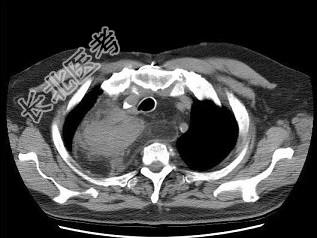

- 单项选择题男,71岁, 消瘦、咳嗽、胸痛,结合胸片和CT, 最可能的诊断是 ( )

A、脂肪肉瘤

B、心包脂肪垫

C、脂肪蓄积症

D、胸腺脂肪瘤

E、胸腺囊肿